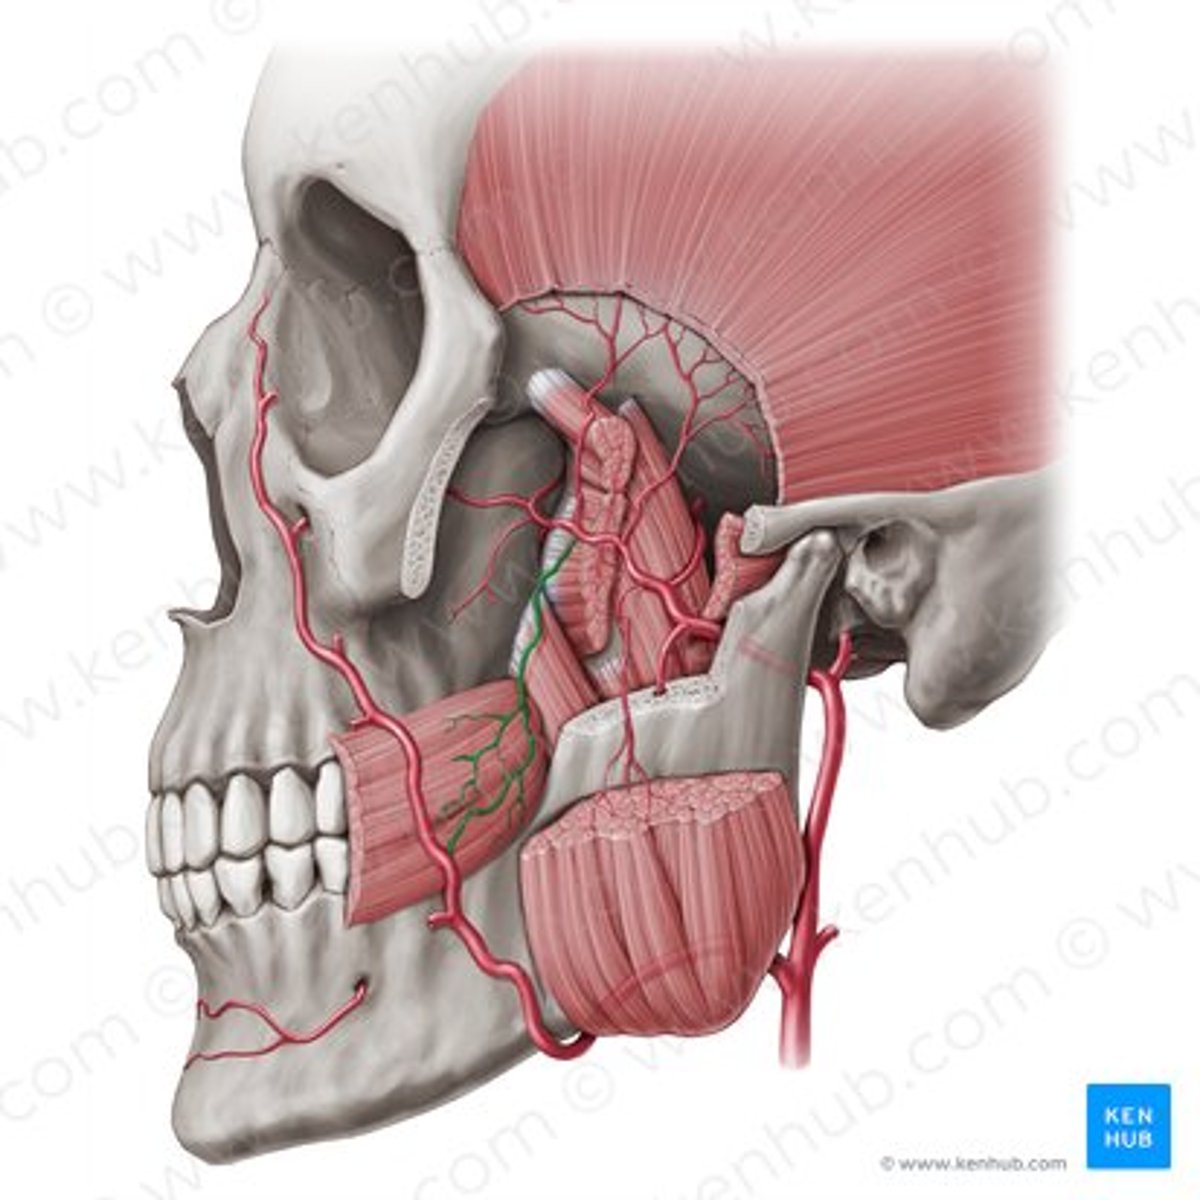

inferior alveolar nerve

inferior alveolar artery

mental nerve

buccal artery

buccal nerve

mandibular foramen